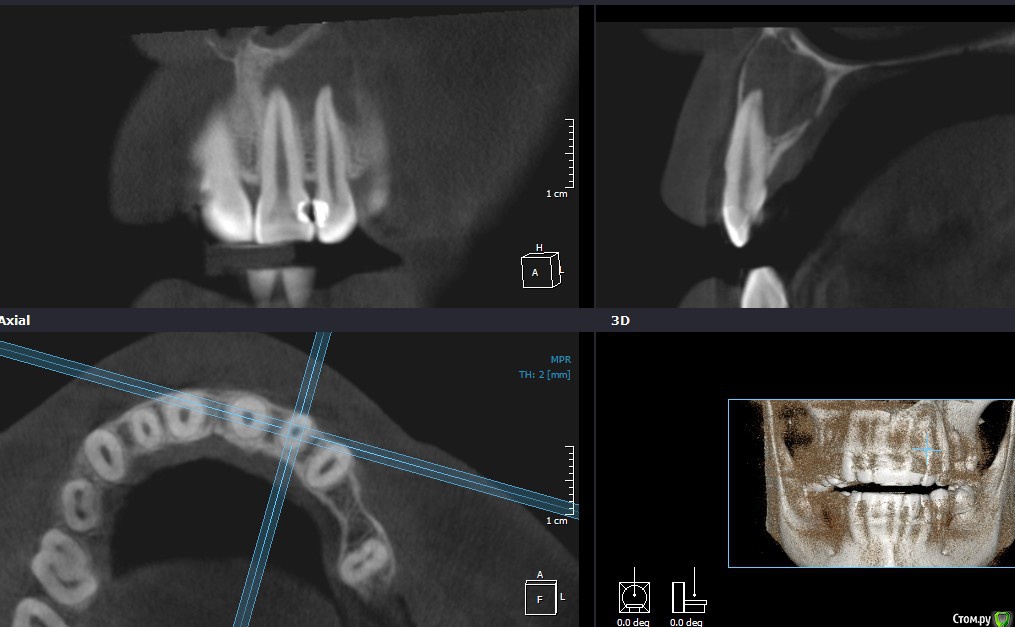

Рустам Опубликовано 17 января, 2016 Поделиться Опубликовано 17 января, 2016 Добрый вечер коллеги! Обратилась пациентка с жалобами на наличие свища в области 22 зуба. Сделали КТ, обширный очаг в области 21, 22. Как считаете, можно попытаться в данной ситуации обойтись консервативным лечением, без хирургии? Ссылка на комментарий